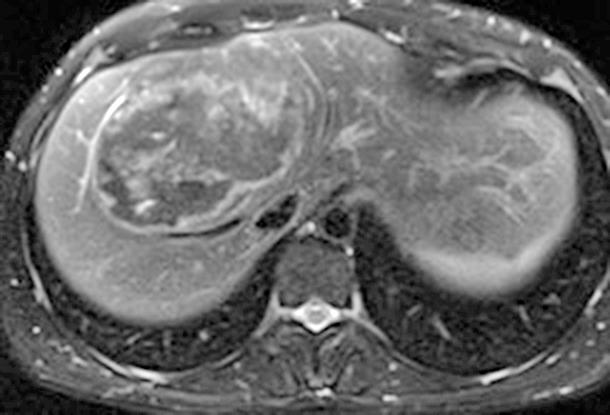

Figura 2 (A y B).

RM: Gran masa hepática localizada en segmentos VII, V y parte del IV. Comportamiento radiológico característico de hepatocarcinoma.

A) T1, imagen hipointensa entre VSH derecha y media.

B) T2, lesión hiperintensa con centro hipointenso.